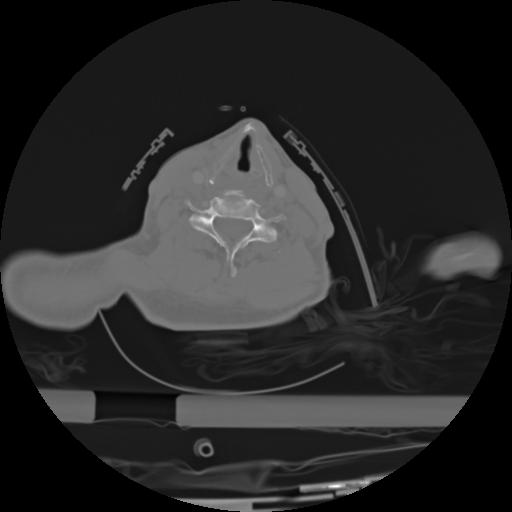

21 ANGIO,CE,Axial,3.0,ANGIO,,